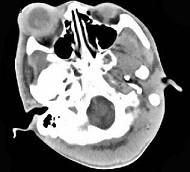

问题 女,24岁,发热畏寒四天,右眼睛疼痛,PE:右眼睑肿胀,结膜充血,伴右眼突出,CT如图所示,应诊断为 ( )

选项 A、眼眶蜂窝织炎 B、眼型Graves病 C、炎性假瘤 D、淋巴瘤 E、Coats病

答案 A